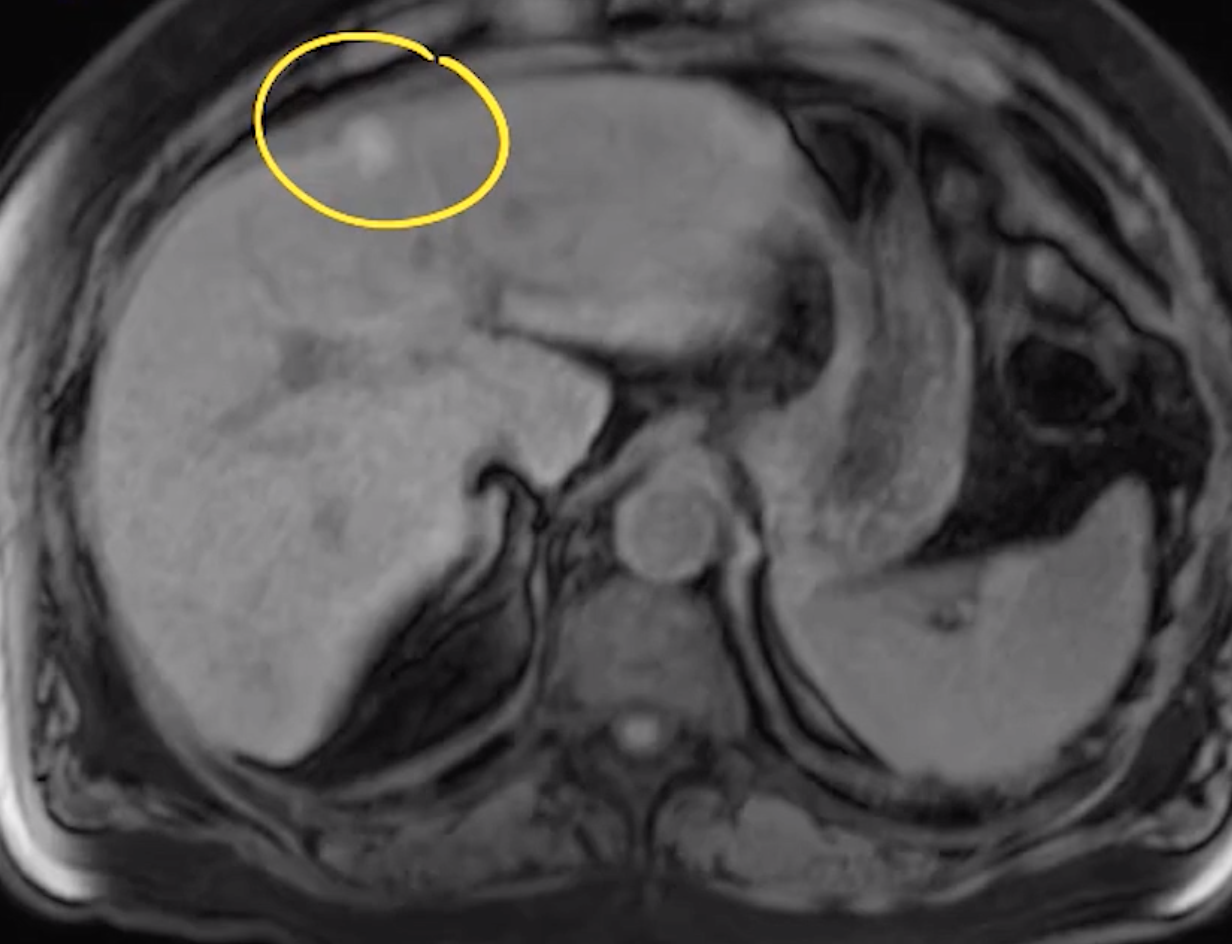

Hemangioma

• Disorganized mass of blood vessels ultimately supplied by the hepatic artery

• Commonly peripheral in liver

• T1: hypointense (relative to liver parenchyma)

• T2: hyperintense (relative to liver parenchyma)

• T1 C +: peripheral nodular discontinuous enhancement with centripetally filling

• Retain contrast on delayed sequences